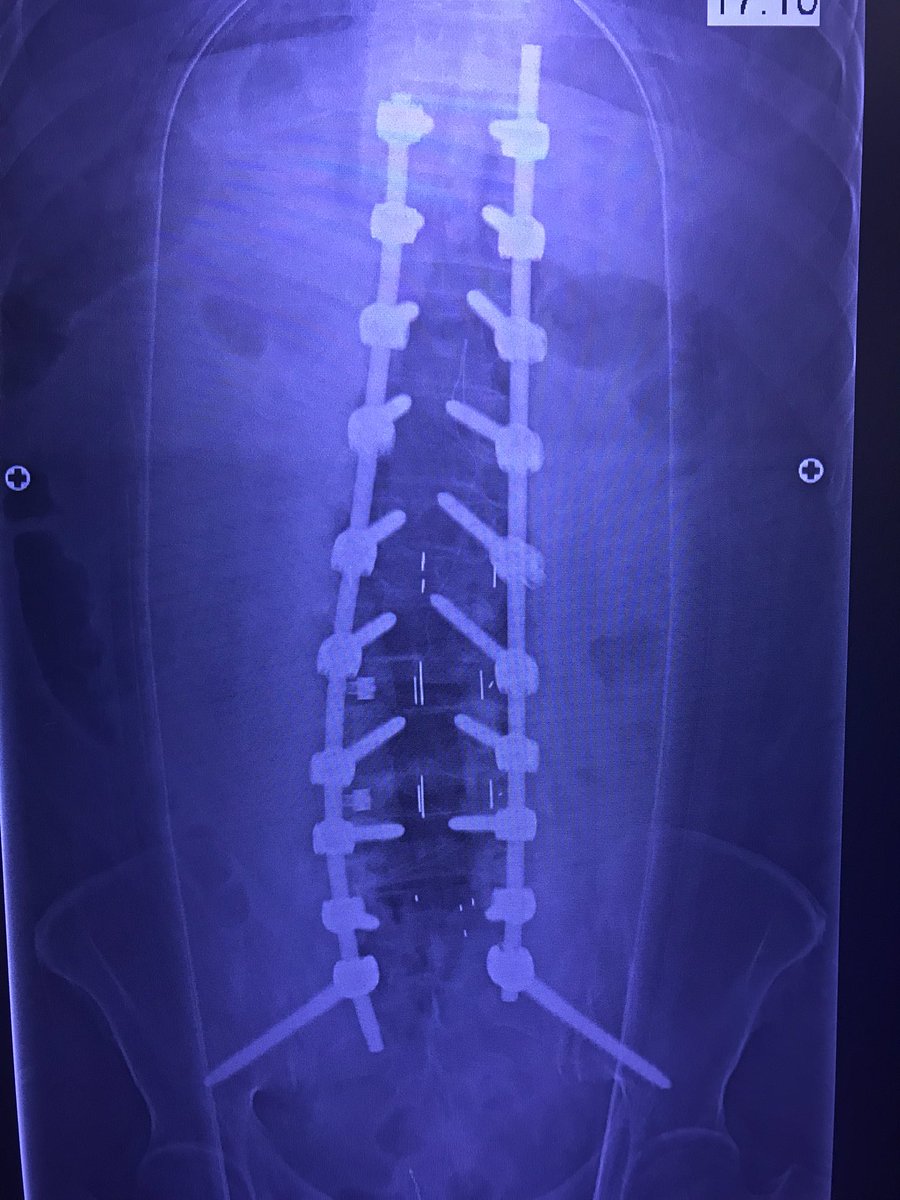

Nice cases before the summer break

jasonpycheung's tweet image. Nice cases before the summer break